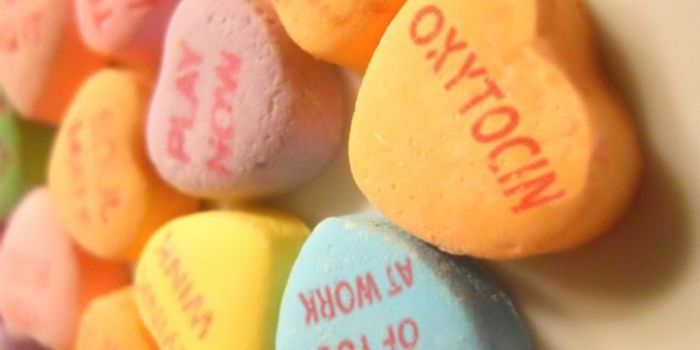

APR 16, 2015NeuroscienceNeuroscientists at NYU Langone Medical Center have discovered how the powerful brain hormone oxytocin acts on individual ...